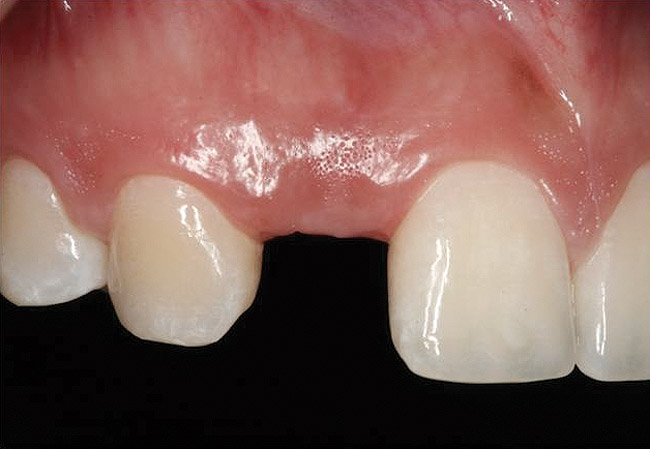

Figure 6  Characterization of the interproximal bone and tooth contacts: A periapical radiograph assists in measuring the distance from bone crest to the adjacent tooth contact points for missing tooth No. 8. The mesial bone crest to the adjacent tooth contact distance is < 5 mm, while the distal bone crest to adjacent tooth contact distance is > 6 mm (Fig 4). One-year following implant placement, conservation of these dimensions is revealed (Fig 5). The clinical photograph (Fig 6) of the lateral incisor adjacent to tooth No. 8 implant crown demonstrates that the absence of distal interproximal (papilla) fill related to the observed bone crest to contact distance exceeds 6 mm.

Figure 6